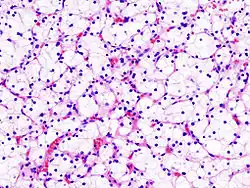

Jest to najczęstszy typ raka nerki i stanowi około 70–80% przypadków[45]. Występuje w korze nerki, najczęściej w pojedynczych ogniskach. Występowanie obustronne lub wieloogniskowe stanowi poniżej 5% przypadków i zwykle wiąże się z predyspozycją dziedziczną (np. zespołem von Hippla-Lindaua)[1]. Makroskopowo guz wielobarwny, żółty do pomarańczowego, często są obecne ogniska martwicy, zmiany krwotoczne, zwapnienia i torbiele[1][46]. Zazwyczaj granice guza są wyraźne[1]. Rozmiar zmiany nie jest wyznacznikiem złośliwości, jednak większy rozmiar guza wiąże się z większym ryzykiem obecności przerzutów[1]. Powiększając się, zajmuje układ kielichowo-miedniczkowy i może wnikać do moczowodu. Stosunkowo często wrasta w żyłę nerkową, sięgając żyły głównej dolnej, a sporadycznie nawet do prawego przedsionka. Przerzuty daje głównie drogą krwionośną poprzez żyłę główną dolną do płuc[1]. Możliwe jest również szerzenie się przerzutów poprzez żyły przykręgosłupowe, żyły jądrowe/jajnikowe, poprzez moczowód i drogą naczyń limfatycznych[1]. Zdarzają się późne przerzuty rozpoznawane nawet po dziesięciu latach choroby[1]. Mikroskopowo nowotwór składa się z komórek o jasnej lub ziarnistej kwasochłonnej cytoplazmie. Jasny wygląd cytoplazmy wynika z nagromadzenia się w niej lipidów i glikogenu, które zostają usunięte na skutek rozpuszczenia w alkoholu podczas rutynowego odwadniania preparatu[1][46]. Jądra są ułożone centralnie; cechują się zróżnicowanym wyglądem i mogą być od małych, drobnych, bez jąderek do dużych, nadbarwliwych i nieregularnych[1]. Podścielisko jest skąpe z siatką cienkościennych naczyń włosowatych, charakterystyczną dla tego typu nowotworu[1]. Komórki tworzą poronne cewki, sznury, wyścielają torbiele lub są chaotycznie ułożone[46].

Jest to drugi co do częstości guz nerki, stanowi około 10–15% przypadków choroby[1][45]. Makroskopowo zwykle to pojedynczy guz z gruboziarnistą i kruchą powierzchnią utworzoną przez brodawki. Często występują torbiele, ogniska martwicy oraz zmiany krwotoczne[1]. Możliwe jest występowanie wieloogniskowe i obustronne guza[46], które spotyka się częściej niż w raku jasnokomórkowym i innych typach raka nerki[1]. Nowotwór jest zbudowany z drobnych sześciennych komórek ze skąpą cytoplazmą tworzących struktury brodawkowate z centralnie położonym naczyniem i luźną tkanką łączną. W podścielisku występują nacieki z makrofagów i neutrofilów[46].